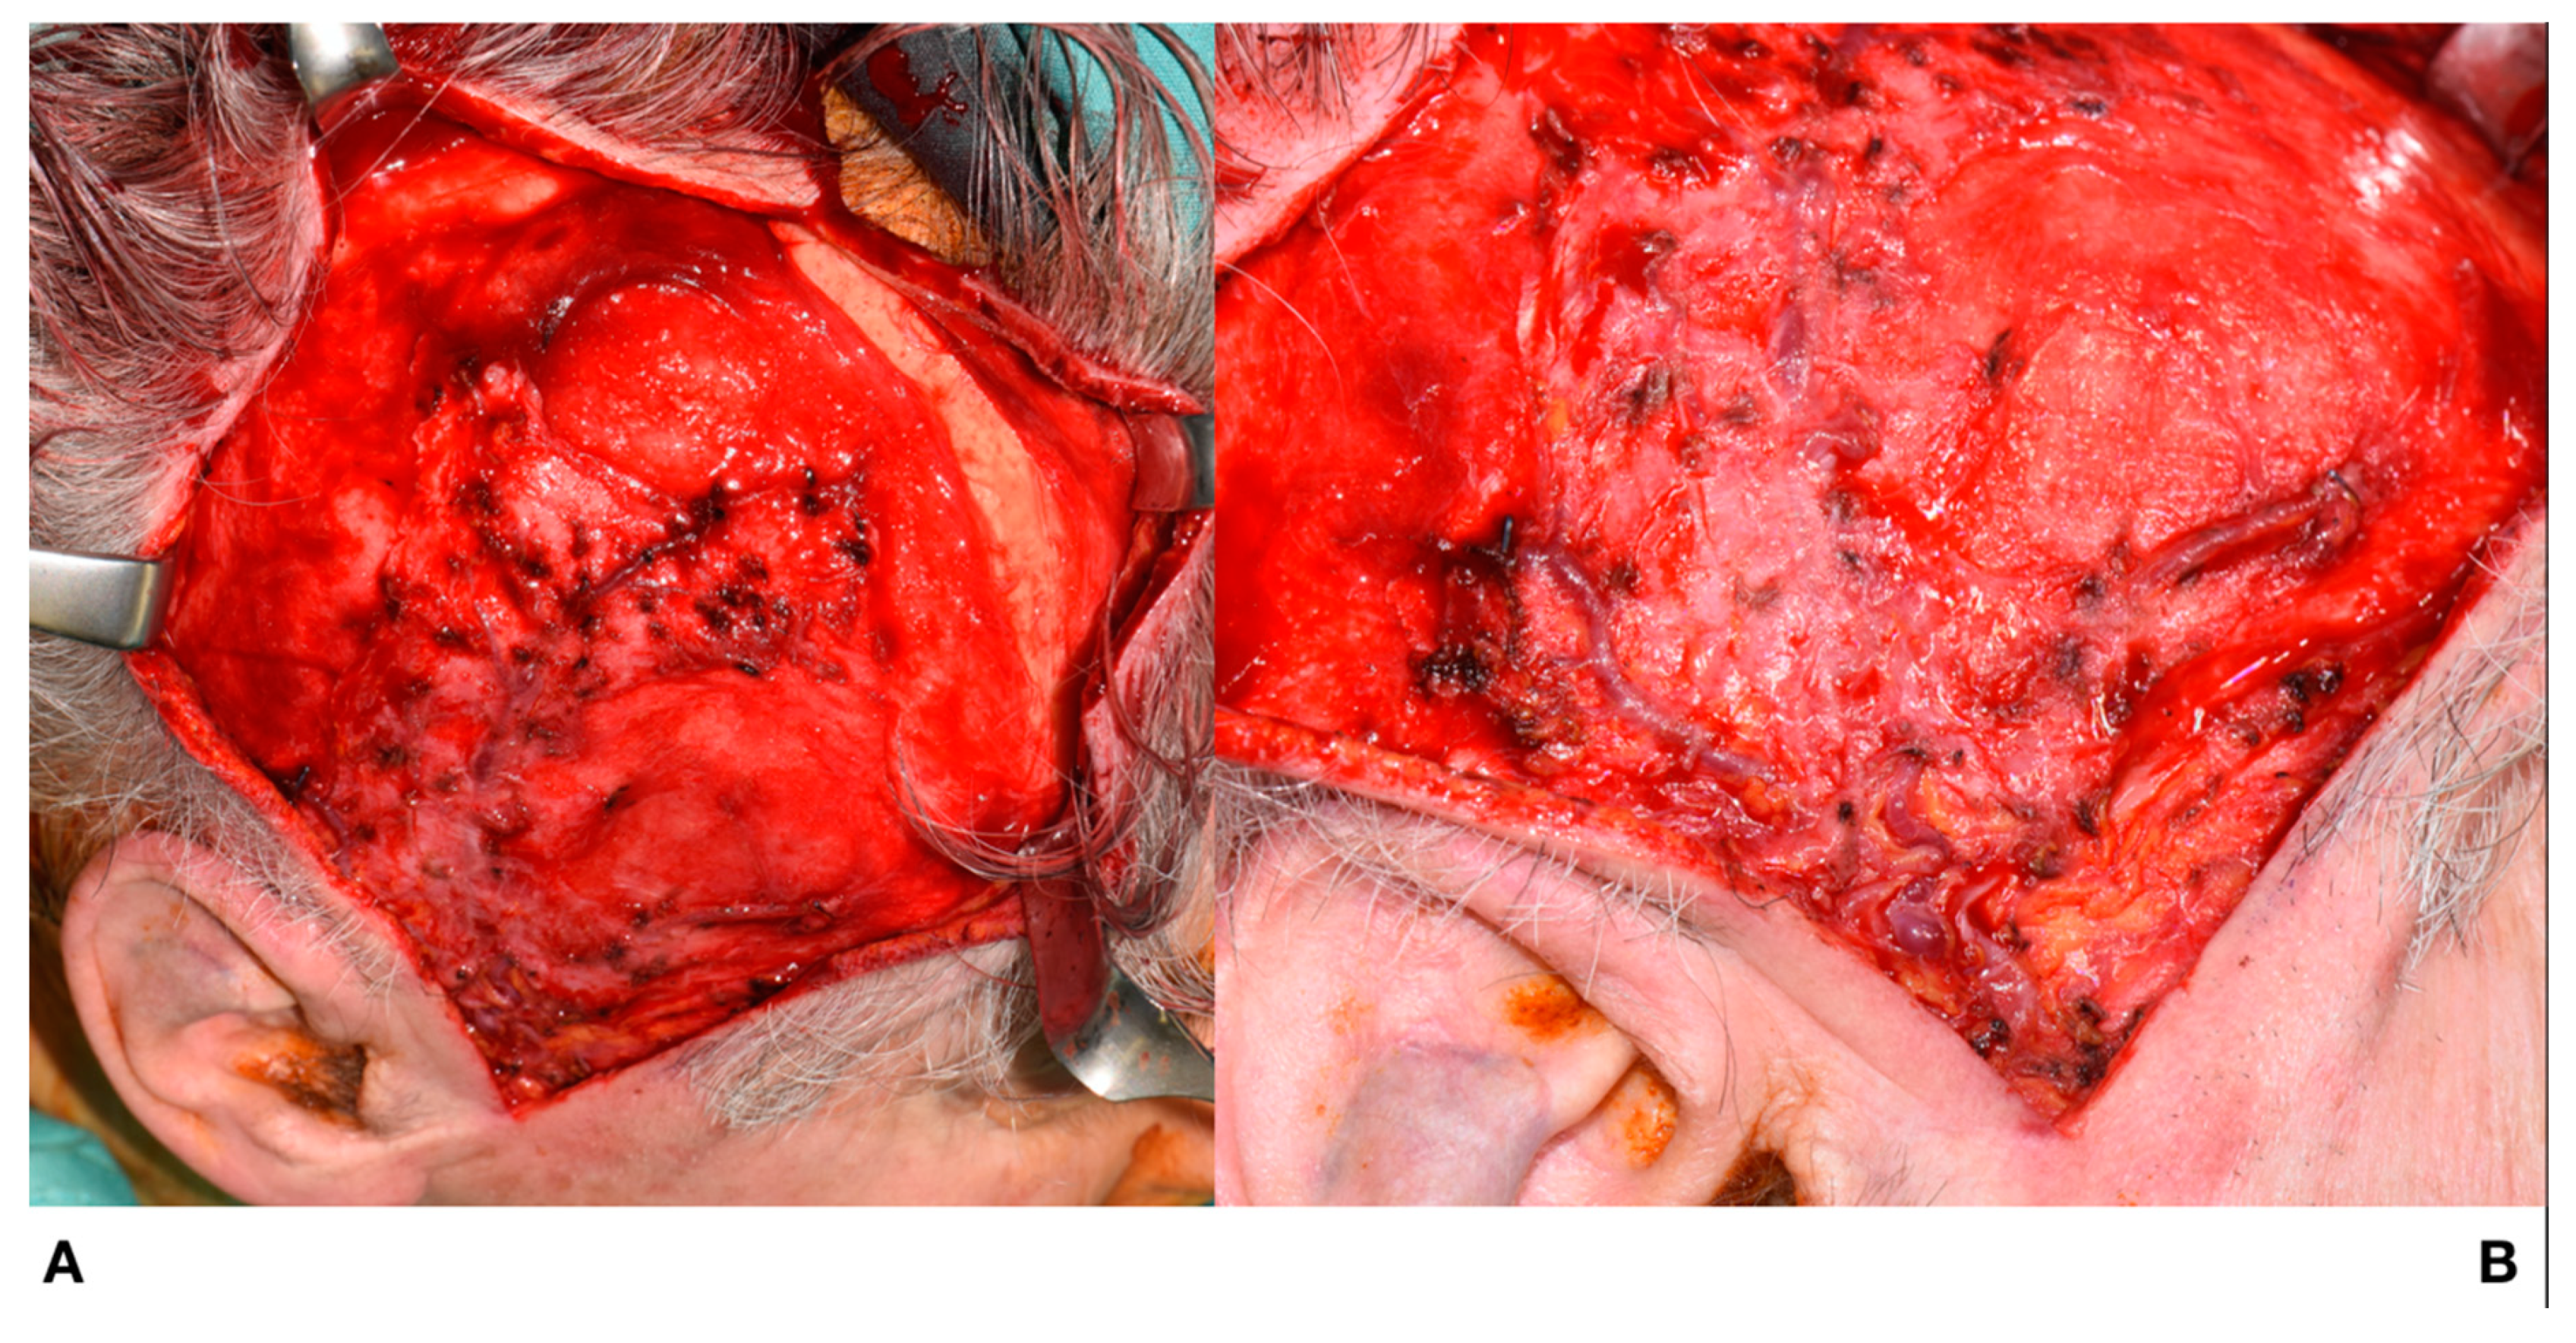

The surgical access route was the same as for harvesting a muscle rotation flap, that is, the incision extended from the preauricular region to the upper temporoparietal skin. After incising the skin in the preauricular region, the main trunks of the STA and STV were separated, and the skin flap was elevated by sharp dissection along the subcutaneous layer to preserve the superficial temporalis blood supply. After achieving the extended surgical exposure required to raise a galea-pericranium flap, the pericranium was incised and detached from the bone, with great care being taken to preserve tissue integrity, as shown in Figure 3.

Figure 3.

(A): The pericranium is incised followed by blunt dissection of the pericranium from the bone. (B): Skin flap showing preserved superficial temporalis vessels.

It was now possible to totally isolate the vessels of the preauricular region. This allowed us to complete harvesting and mobilisation of the deep portion of the galea-pericranium flap, as shown in Figure 5.

Figure 5.

Raising of the flap. (A): Superficial view. (B): Deep view.